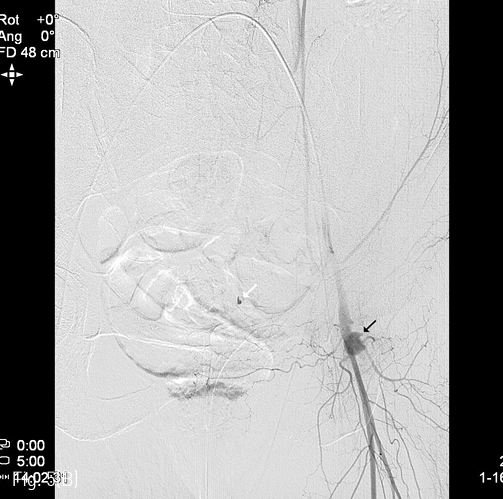

입원 중 발생한 복부와 하지의 반상출혈 및 헤모글로빈 감소로 시행한 CT에서 우측 장골회선동맥(deep circumflex iliac artery)에서의 활동성 출혈 및 우측 복벽의 혈종(13 x 9cm)이 확인되어 (Fig. 1A), Glue를 이용하여 색전술을 시행하였다(Fig. 1B). 최초 증상발생일을 기준으로 7일째 재발한 증상으로 촬영한 CT에서 혈종의 크기가 증가하였으며 (26 x 12cm), 우측 하복벽동맥(inferior epigastric artery)의 출혈병소가 관찰되어(Fig. 2A), Glue를 이용하여 2차 색전술을 시행하였다 (Fig. 2B). 다시 11일째 증상 재발하여 시행한 CT에서 혈종은 좌측 복벽에도 발생한 상태였으며 활동성 출혈병소는 우측에서만 확인되어 (Fig. 3A) 3차 응급색전술을 시행하였다. 혈관조영시 우측 장요동맥(iliolumbar artery)에서 혈관외유출이 확인되어 다시 Glue를 이용하여 색전술을 시행하였으며 (Fig. 3B), 좌측 복벽혈종의 원인 혈관은 보이지 않았다. 다시 15일째 같은 원인으로 시행한 CT에서 복벽혈종은 좌우가 연결되어 복강내 장기들을 압박하고 있었으며 크기는 약 31 x 15cm까지 커져있는 상태였고 (Fig. 4A), 좌측 서혜부에 활동성 출혈병소가 확인되어(Fig. 4B) 응급혈관조영술을 시행하였다. 혈관조영술에서 근위부 대퇴동맥과 대퇴회선 동맥(circumflex femoral artery)의 작은 분지에서 출혈병소가 확인되었으며, 각각에 대해 Gelfoam을 이용하여 색전술을 시행하였다 (Fig. 4C). 다시 같은 원인으로 26일째 CT 시행하였으며, 혈종은 더욱 커져 약 34 x 18cm까지 커지고 (Fig. 5A), 배꼽 근방에서는 피부 결손이 발생하였으며, 복강내 장기의 압박으로 양측 수신증까지 발생한 상태였다. 좌측 하복벽동맥에서 기시하는 출혈병소가 의심되었기에 다시 혈관조영술을 시행하였으며, 해당 동맥에 대해 Gelfoam을 이용하여 색전술을 시행하였다 (Fig. 5B). 추가적으로 좌측 대퇴동맥 카테터 삽입부에 가성동맥류가 형성된 것이 확인되었고 보존적으로 추적관찰하기로 하였다. 최초 색전술을 기준으로 29일째 6번째 CT를 촬영하였으며, 우측 상복벽에 새롭게 출혈병소가 확인되었다 (Fig. 6A). 다시 혈관조영술을 시행하였으며, 우측 내흉동맥에서 기시하는 근횡격막동맥 (musculophrenic artery)의 분지에서 출혈병소가 확인되어 Glue를 이용하여 색전술을 시행하였다 (Fig. 6B).

Fig 1B

(B) Multifocal extravasation of contrast media from the small branches on right deep iliac circumflex angiography (arrows), which was followed by glue embolization.